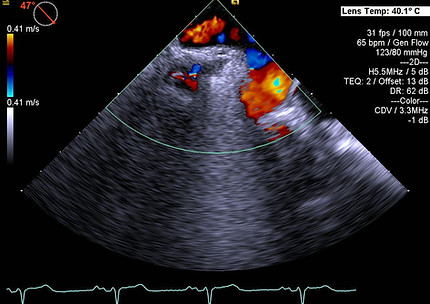

Example of 3 right sided pulmonary veins a right upper (right most), right lower (left most) and middle vein.